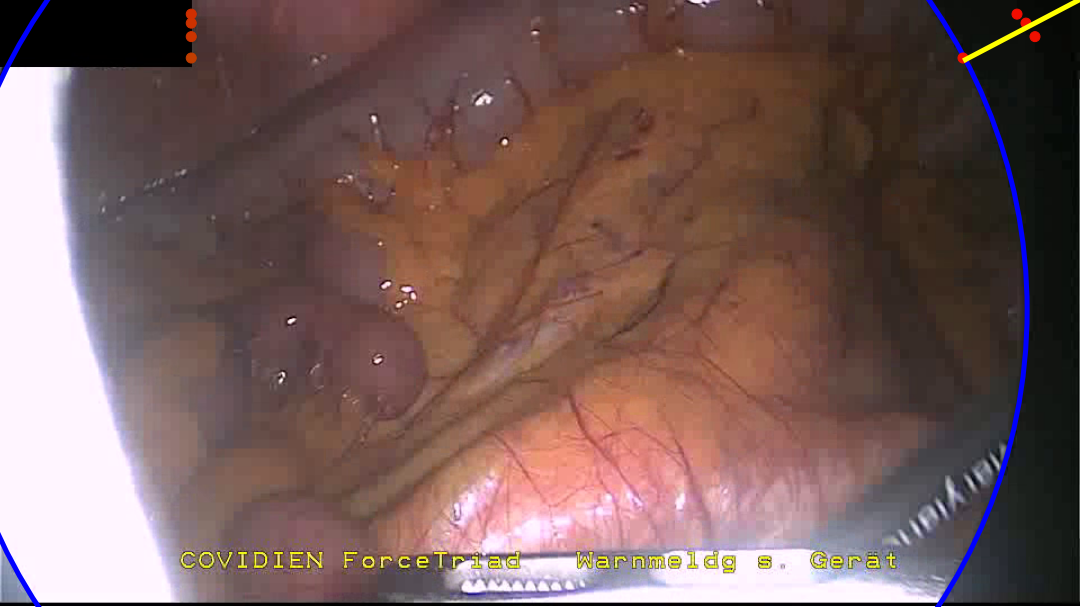

Delineation between the border and the content area of the image is made non-trivial by a few factors. Figure 3 shows a selection of endoscopic images demonstrating some of these difficulties. Firstly, while the border is generally a uniform black, a fair amount of low level noise is often observed, and imperfections in the scopes optics can result in aberrations such as bright spots, diffuse light bleeding outside of the content area, or imperfect circles. Secondly, the image within the content area may be adverse in that it can have low brightness or contain within it a secondary circular oculus, such as when the tip of the endoscope is only partially inserted through a trocar. Thirdly, while the circular image projection is generally centred around the middle of the image, it can in fact be significantly offset from the centre and its radius can fall within in a large range, even passing beyond the horizontal extent of the image for much of the image height. The spatial position and size of the circular image projection may also be surprisingly dynamic throughout an intervention, varying due to mechanical stresses placed through the endoscope and as the operator adjusts the zoom level on the camera. Finally, there can exist additional overlays such as secondary camera feeds, logos, and text.

Refer to caption

(a) A saturated area at the edge of the content area bleeds into the border.

(b) A dark content area leaves only a small segment of the circle visible.

(c) A partially cropped circle combined with a black overlay.

(d) Text overlays the content area and border.

(e) Structure within the top right quadrant of the content area appears as a misleading circle segment.

(f) A dark content area combined with a mostly cropped border provides a truly challenging example.

Figure 3: A selection of examples taken from our hand annotated dataset, chosen to portray some of the adverse features faced during endoscopic content area estimation.